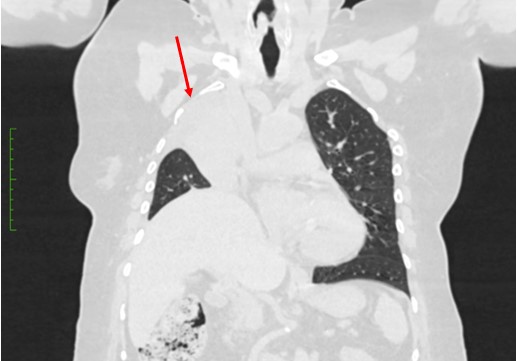

Rezultat – 3 mjeseca nakon RK

djelomično reventiliran desni gornji plućni režanj